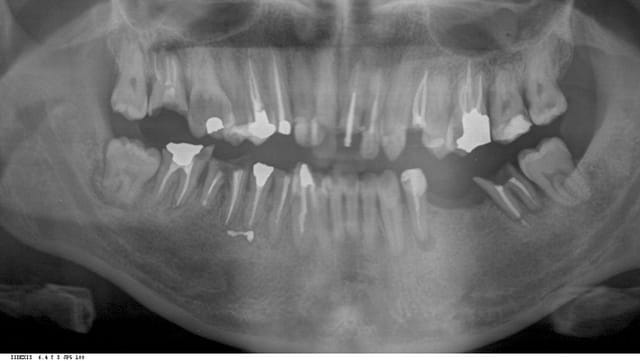

la pano

je crois que là, à part dentisterie véto et pédo, tu as tous les thèmes d'eugénol dans une seule bouche.

ensuite comment la mécanique alhounienne va t elle s'epanouir et se révéler? par exemple, mais entre autre, va t y se bagarrer avec cette 34 en reprenant l'endo et en esperant resurrection (c'est jouable), va t y virer et implanter avec le reste (il y a tellement d'os si tentant)? comment l'endo qui est au plus profond de lui va t il se confronter avec l'implanto encore plus enfoui?

Le premier truc qui m'interpelle, c'est les photos avec le contraste de certains traitements radiculaires

A mon avis alhoun il a pris la pano a la moitié du traitement, car aucune raison que 34 ne soit pas retraitée comme 17.

Si le patient me promet qu'il a arreter les stups, vac preuves sanguines a l'appuis je me lance, et j'ai quelque doute sur 37, mais dans l'ensemble tout me semble sauvegardable sauf 48 , bien sur si c'est Alhoun qui a fait les traitements d'endo ou son correspondant endo pour savoir si le patient a du repondant.

Même pas sur d'avoir a augmenter la dv , vu comment il vafalkloir retablir le rapport couronne racine en haut

Allez deux implants en bas a droite et une vingtaine de procera et c'est bon